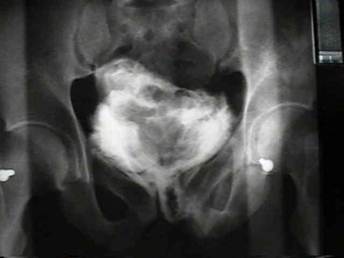

Ретроградная цистография. В данном методе используют контрастное вещество, вводимое в мочевой пузырь ретроградно по катетеру. Для этого после установки мочевого катетера, разводят контрастное вещество в 300мл физ.р-ра, фурацилина или др., которое вводят в мочевой пузырь. Накладывают зажим. Производят обзорные рентген снимки костей таза в прямой и под углом 45 градусов проекциях (рис.16). При целом мочевом пузыре на цистограмме его контур равный, без деформаций, в виде шара. При разрыве - контур неровный, имеются его деформации, затеки контрастного вещества (рис. 17). Метод является достоверным.

Рис.16. Ретроградная цистография в прямой и под углом 45 проекциях, а также позиция больного для проведения последней.

Рис.17. Ретроградная цистография в прямой проекции с разрывом мочевого пузыря.